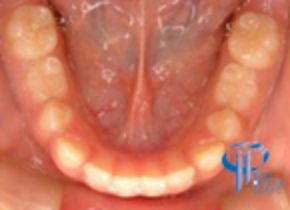

治療後

上下4前歯計8本を正常な咬合にすることにより、歯性から生じた下顎前突の問題は解消されました。

今後、骨格性の問題が発症しないか、経過観察は必要です。

8才男性 上顎前歯の前方移動を可撤式装置で行い、正常被蓋を獲得した |

10ヶ月 |